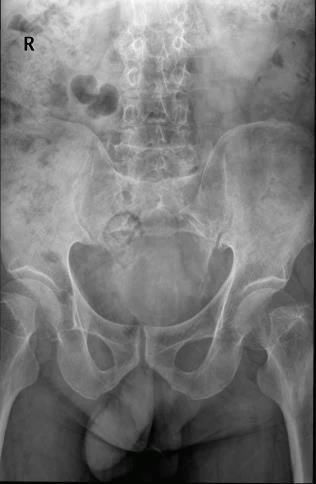

Case6:M,61y;骶尾椎疼痛2年。

文章插图